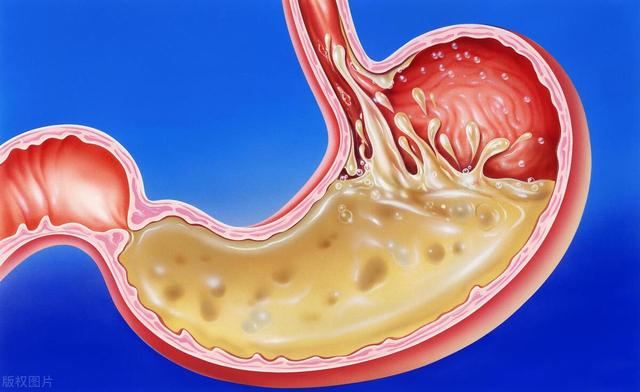

回到家后,李大爷迫不及待地开始上网搜索相关信息。他了解到,随着年龄的增长,老年人的消化系统功能逐渐下降,对某些食物的耐受能力也会降低。中国营养学会发布的《中国居民膳食指南(2022)》特别强调了老年人饮食的特殊性,建议老年人选择易消化、富含营养的食物。

精白米虽然口感好,易消化,但营养成分相对较少。过多食用可能导致血糖快速升高,不利于糖尿病的控制。一项研究显示,长期大量食用精白米可能增加老年人患2型糖尿病的风险。

精制面粉制品,如白面馒头、白面包等,同样存在营养不足的问题。这些食品纤维含量低,容易导致便秘,而老年人本就容易出现便秘问题。一项研究发现,增加膳食纤维摄入可以有效改善老年人的便秘症状。

听完张医生的解释,李大爷恍然大悟。他想起自己最近总觉得消化不良,原来可能与这些主食有关。张医生建议李大爷可以多食用小米粥作为主食替代。

小米营养丰富,含有丰富的膳食纤维、维生素和矿物质。它的颗粒小,煮成粥后易于消化吸收,非常适合老年人食用。一项研究表明,小米中含有的黄酮类化合物具有抗氧化作用,可能有助于预防老年性疾病。